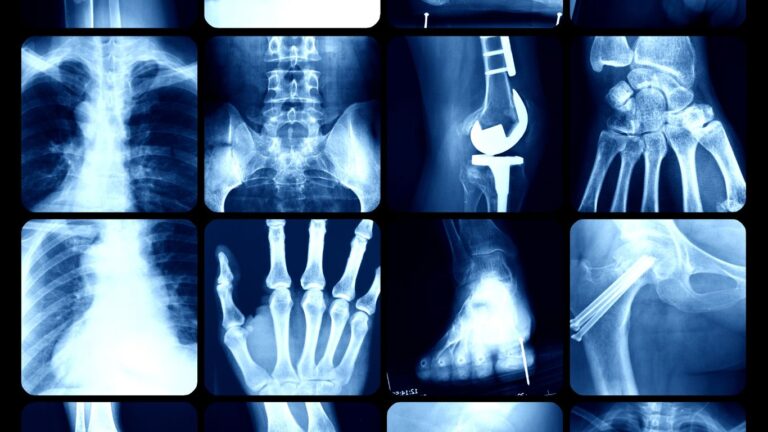

En el ámbito médico, es esencial comprender qué se ve en los rayos X. Estas imágenes radiográficas nos permiten observar estructuras visibles como huesos, órganos internos y en algunos casos, tejidos blandos. El principio detrás de este proceso radiológico radica en la diferente densidad de los materiales dentro del cuerpo humano, lo que permite a los profesionales de la salud obtener información vital para su diagnóstico.

Estructuras visibles en las imágenes

Las imágenes de rayos X son fundamentales para identificar estructuras visibles. Pueden revelar fracturas, desgarros y malformaciones óseas de manera clara. También permiten evaluar los pulmones, el corazón y otros órganos vitales, proporcionando a los médicos una base sólida para tomar decisiones clínicas. La claridad de estas imágenes ayuda en la detección y monitoreo de varias condiciones de salud.

¿Cómo nos ayudan los rayos X a cuidar nuestros huesos?

Los rayos X son fundamentales en el cuidado de nuestra salud ósea. A través de ellos, podemos obtener imágenes claras que permiten identificar problemas en los huesos. Esto es crucial para tomar decisiones informadas sobre el tratamiento y el cuidado necesario para mantener nuestro bienestar.

Detección de fracturas y lesiones

Gracias a su capacidad para mostrar el estado interno de nuestros huesos, los rayos X facilitan la detección de fracturas y lesiones. Ante un accidente o dolor repentino, estas imágenes se convierten en una herramienta necesaria para evaluar el daño y proceder con las intervenciones adecuadas.

Monitoreo de la salud ósea

Los rayos X también juegan un papel importante en el monitoreo de salud ósea, especialmente en condiciones como la osteoporosis. Mantener un seguimiento regular de la densidad ósea nos permite prevenir complicaciones futuras y actuar proactivamente para proteger nuestros huesos.